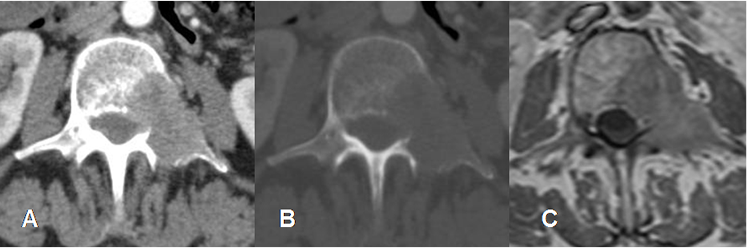

Fig 29. Metástasis líticas.

A: TAC axial en ventana de tejido. B: TAC axial en ventana de huesos y C: RM axial en T1 con contraste. Lesión lítica que compromete el cuerpo, el pedículo y la apófisis transversa de L2. Hay masa de tejidos blandos que ocupa el agujero de conjunción y el canal, la cual realza con el contraste, por metástasis lítica de Ca broncogénico.